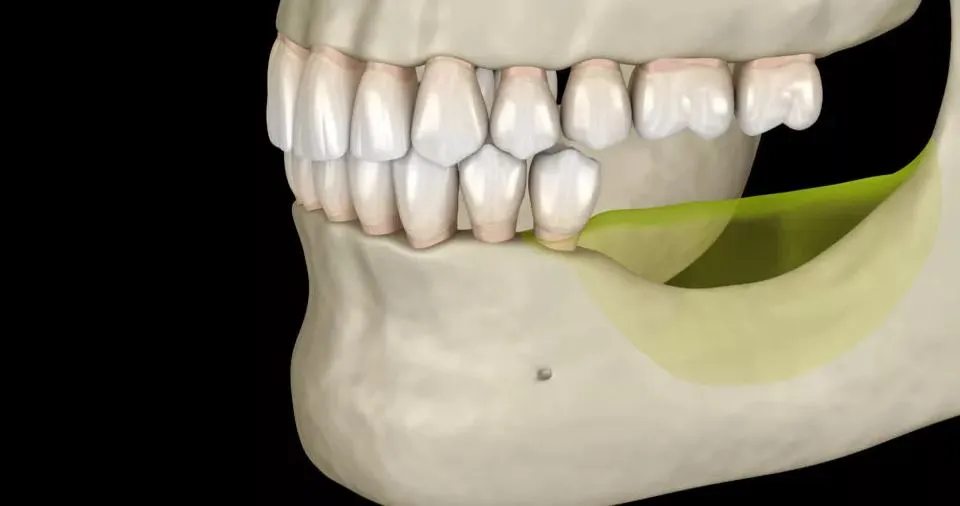

زراعة عظم الفك أو ما يُعرف بتطعيم عظم الفك هي إجراء طبي يستخدم لتعويض النقص أو فقدان العظم في منطقة الفك، سواء بسبب تسوس الأسنان، أمراض اللثة، أو فقدان الأسنان الطويل المدى، يهدف هذا الإجراء إلى تهيئة قاعدة قوية ومستقرة لتثبيت غرسات الأسنان بشكل آمن ودائم.

يتم خلال العملية استخدام عظم طبيعي من جسم المريض أو عظم صناعي لتعويض الجزء المفقود، ويساعد هذا على استعادة شكل الفك الطبيعي ودعم صحة الفم بشكل عام، يساهم تطعيم عظم الفك أيضاً في الحفاظ على التوازن الوظيفي والجمالي للفم، الأمر الذي يجعل المرضى قادرين على استعادة الابتسامة الطبيعية والقدرة على المضغ بشكل سليم.

زراعة العظم قبل زراعة الاسنان خطوة مهمة لضمان ثبات الغرسة ونجاح العملية، خصوصاً في الحالات التي يعاني فيها المريض من نقص أو فقدان كثافة العظم في الفك، تساعد هذه التقنية على خلق قاعدة صلبة تدعم الغرسة وتضمن مظهر طبيعي للفك.

تلجأ إلى زراعة العظم للأسنان في حالات متعددة عندما يكون حجم أو كثافة عظم الفك غير كافية لدعم الغرسة السنية بشكل آمن وفعال، يحدث هذا النقص عادةً بسبب فقدان الأسنان لفترة طويلة، حيث يؤدي غياب الأسنان إلى انحسار العظم مع مرور الوقت، الأمر الذي يجعل تركيب الغرسة مباشرة غير ممكن، كما يمكن أن يكون سبب الحاجة إلى زراعة العظم أمراض اللثة المزمنة التي تؤدي إلى تآكل العظم الداعم للأسنان، أو إصابات الفك والحوادث التي تسبب فقدان جزء من العظم، في بعض الحالات، قد يكون العظم ضعيف أو رقيق طبيعي عند بعض الأشخاص، الأمر الذي يستدعي التدخل قبل زراعة الأسنان.

الهدف من زراعة العظم قبل الغرسة هو توفير قاعدة قوية ومستقرة للزرعة، يضمن بذلك ثباتها على المدى الطويل ويقلل من مخاطر فشل العملية، كما تساعد هذه التقنية في الحفاظ على المظهر الطبيعي للفك والوجه، ومنع تغيرات شكلية قد تنتج عن فقدان العظم، مع دعم الوظائف الفموية الأساسية مثل المضغ والكلام، لذلك يعتبر تطعيم العظم خطوة أساسية وبالتالي يضمن نجاح عملية زراعة الأسنان وتحقيق أفضل النتائج الجمالية والصحية للمريض.

زراعة عظم الفك، أو تطعيم العظم هي إجراء طبي يستخدم لتعويض نقص العظم في الفك بهدف توفير قاعدة صلبة وآمنة لدعم غرسات الأسنان، يستخدم فيها عظم طبيعي مأخوذ من جسم المريض أو عظم صناعي، ويهدف إلى استعادة الشكل الطبيعي للفك والحفاظ على الوظائف الفموية مثل المضغ والكلام، مع تمكين الغرسة السنية من الثبات على المدى الطويل.

تلجأ إلى زراعة العظم قبل زراعة الأسنان في الحالات التي يكون فيها حجم أو كثافة العظم غير كافية لدعم الغرسة، الأسباب الأكثر شيوعاً تشمل فقدان الأسنان لفترة طويلة، تآكل العظم الناتج عن أمراض اللثة المزمنة، الإصابات أو الحوادث التي تؤدي إلى فقدان جزء من الفك، أو ضعف العظم الطبيعي عند بعض الأشخاص، هذه الخطوة ضرورية الأمر الذي يضمن ثبات الغرسة واستقرارها ووظائف الفم الطبيعية.